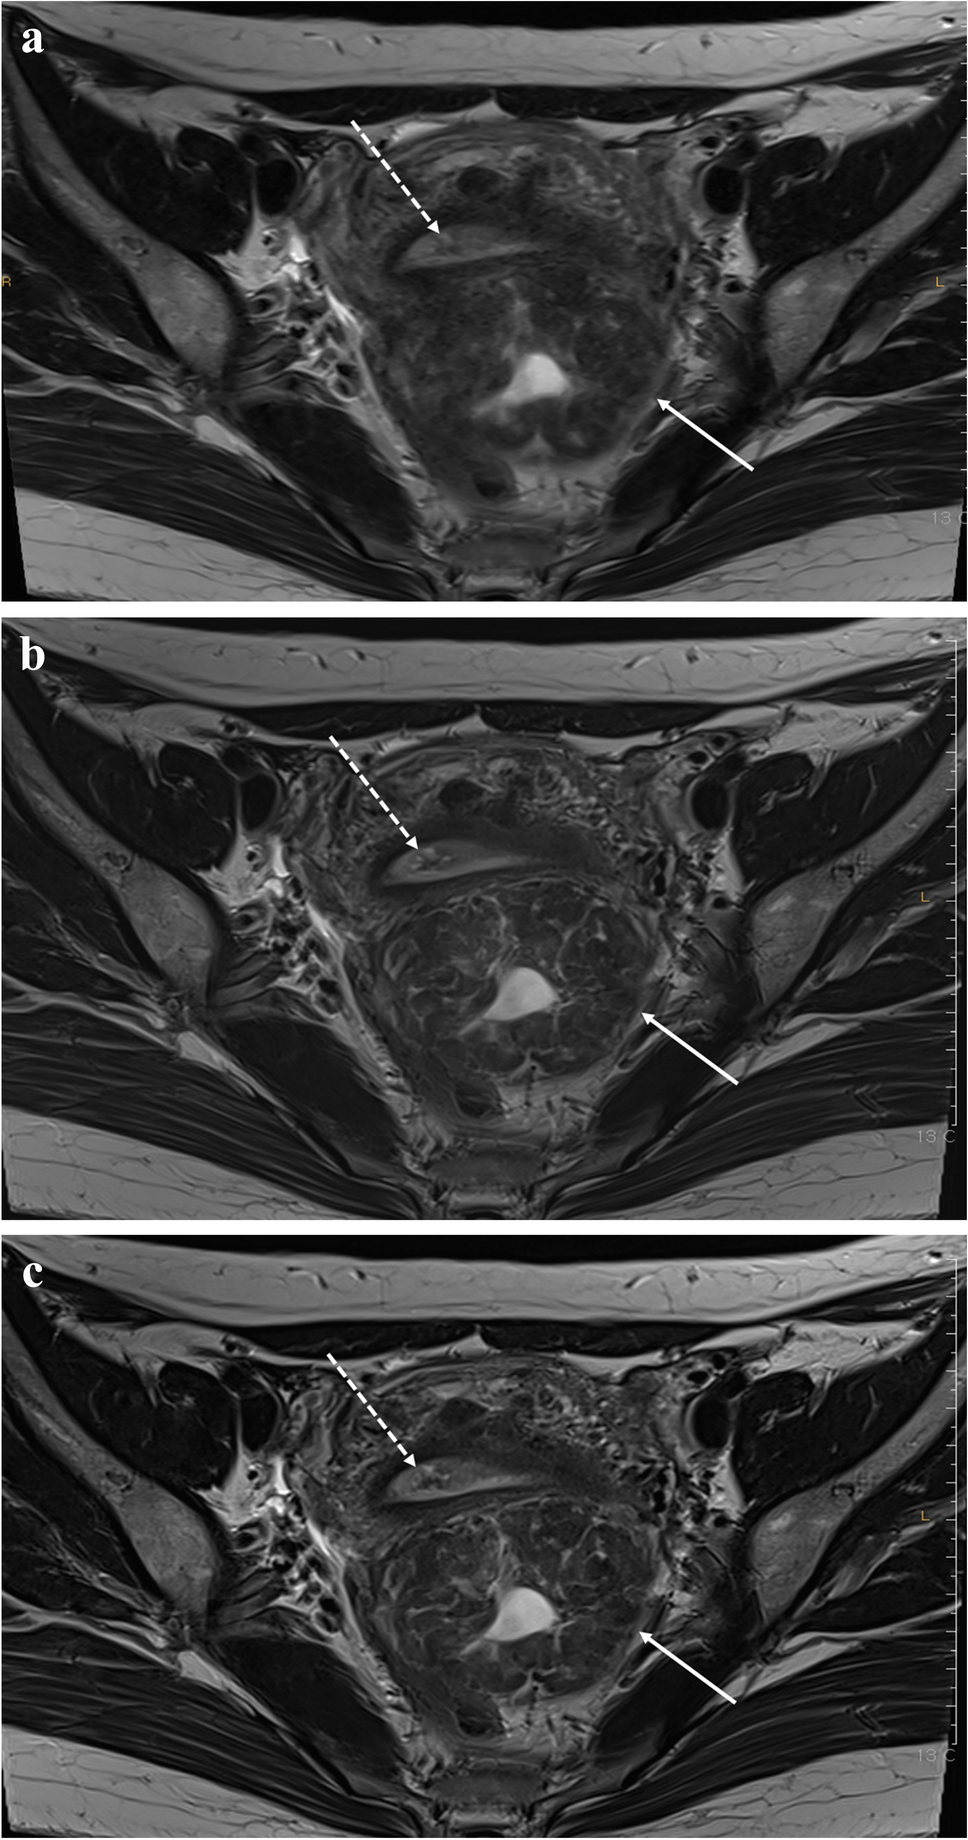

DL適用前後の比較画像

DL適用前後の比較 — SNR改善効果